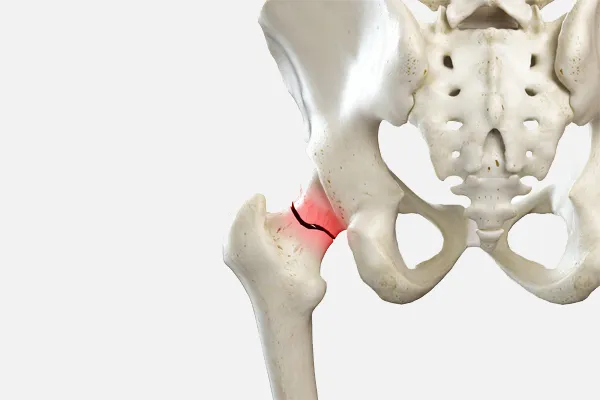

한국인에게 흔한 고관절 질환은 '고관절 충돌 증후군', '고관절 골관절염', '대퇴골두 무혈성 괴사' 등의 질환입니다. 이외에도 질환은 아니지만 노년기에 골밀도가 감소하면서 낙상으로 인한 '고관절 골절'도 흔한 문제로 나타날 수 있습니다.

고관절을 이루는 비구(골반의 컵 모양 소켓)와 대퇴골두(허벅지 뼈의 공 모양 끝부분), 그리고 경부(대퇴골두와 허벅지 뼈를 연결하는 부위)의 구조가 서로 충돌하면서 통증을 일으키는 질환입니다. 관절 사이의 충돌이 오랜 기간 반복되면 충돌 부위의 관절 연골이 손상되고, 비구(소켓에 붙어 있는 연골)나 대퇴골에 붙어 있는 섬유 연골 조직이 찢어져 통증을 유발할 수 있습니다.